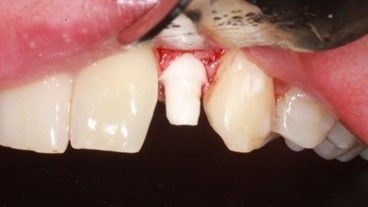

Se presenta un paciente varón de 34 años de edad, no fumador y sin antecedentes médico-quirúrgicos de interés (ASA I), que acudió a la consulta demandando una mejora en la estética de su sonrisa.

El paciente presentaba una agenesia congénita en el incisivo lateral superior izquierdo que había sido tratada previamente con ortodoncia para cerrar dicho espacio.

Tras el examen intraoral del paciente y el estudio radiográfico, se plantea la opción de tratamiento de abrir nuevamente el espacio mediante ortodoncia para rehabilitar la ausencia con un implante de circona, asegurando la estética que demandaba el paciente.

Case description: A clinical case of a 34-year-old man is presented, non-smoker and with no previous registered medical records (ASA I) who came to the dental clinic demanding an improvement in the aesthetics of his smile. The patient had a congenital agenesis of the right lateral incisor that had previously been treated with orthodontics to close the space. After the radiographic study and intraoral examination of the patient, the treatment option of reopening the space with a new phase of corrective orthodontics to rehabilitate the absence with a zirconia implant was proposed, ensuring the aesthetics demanded by the patient.